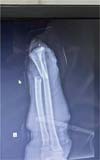

Um paciente (IPB) de 56 anos, do sexo masculino, casado, natural e procedente de Fortaleza, deu entrada no hospital decorrente de acidente por serra em ambiente de açougue. Ele apresentava amputação total da mão esquerda ao nível de punho com exposição óssea e tendínea, com torniquete no esquerdo e mão acondicionada em recipiente com gelo. Relatou que o acidente ocorreu há aproximadamente 40 minutos. Ao exame apresentava-se estável, porém moderadamente hipocorado devido a perda sanguínea significativa, porém sem perda de consciência com frequência cardíaca próximo a 110 bpm se enquadrando em choque hipovolêmico grau 2. Não havia sinais de escoriações ou trauma em outros membros (►Figs. 1-3).

Fig. 2 - Coto proximal do antebraço.

Fig. 3 - Radiografia pré-operatória.